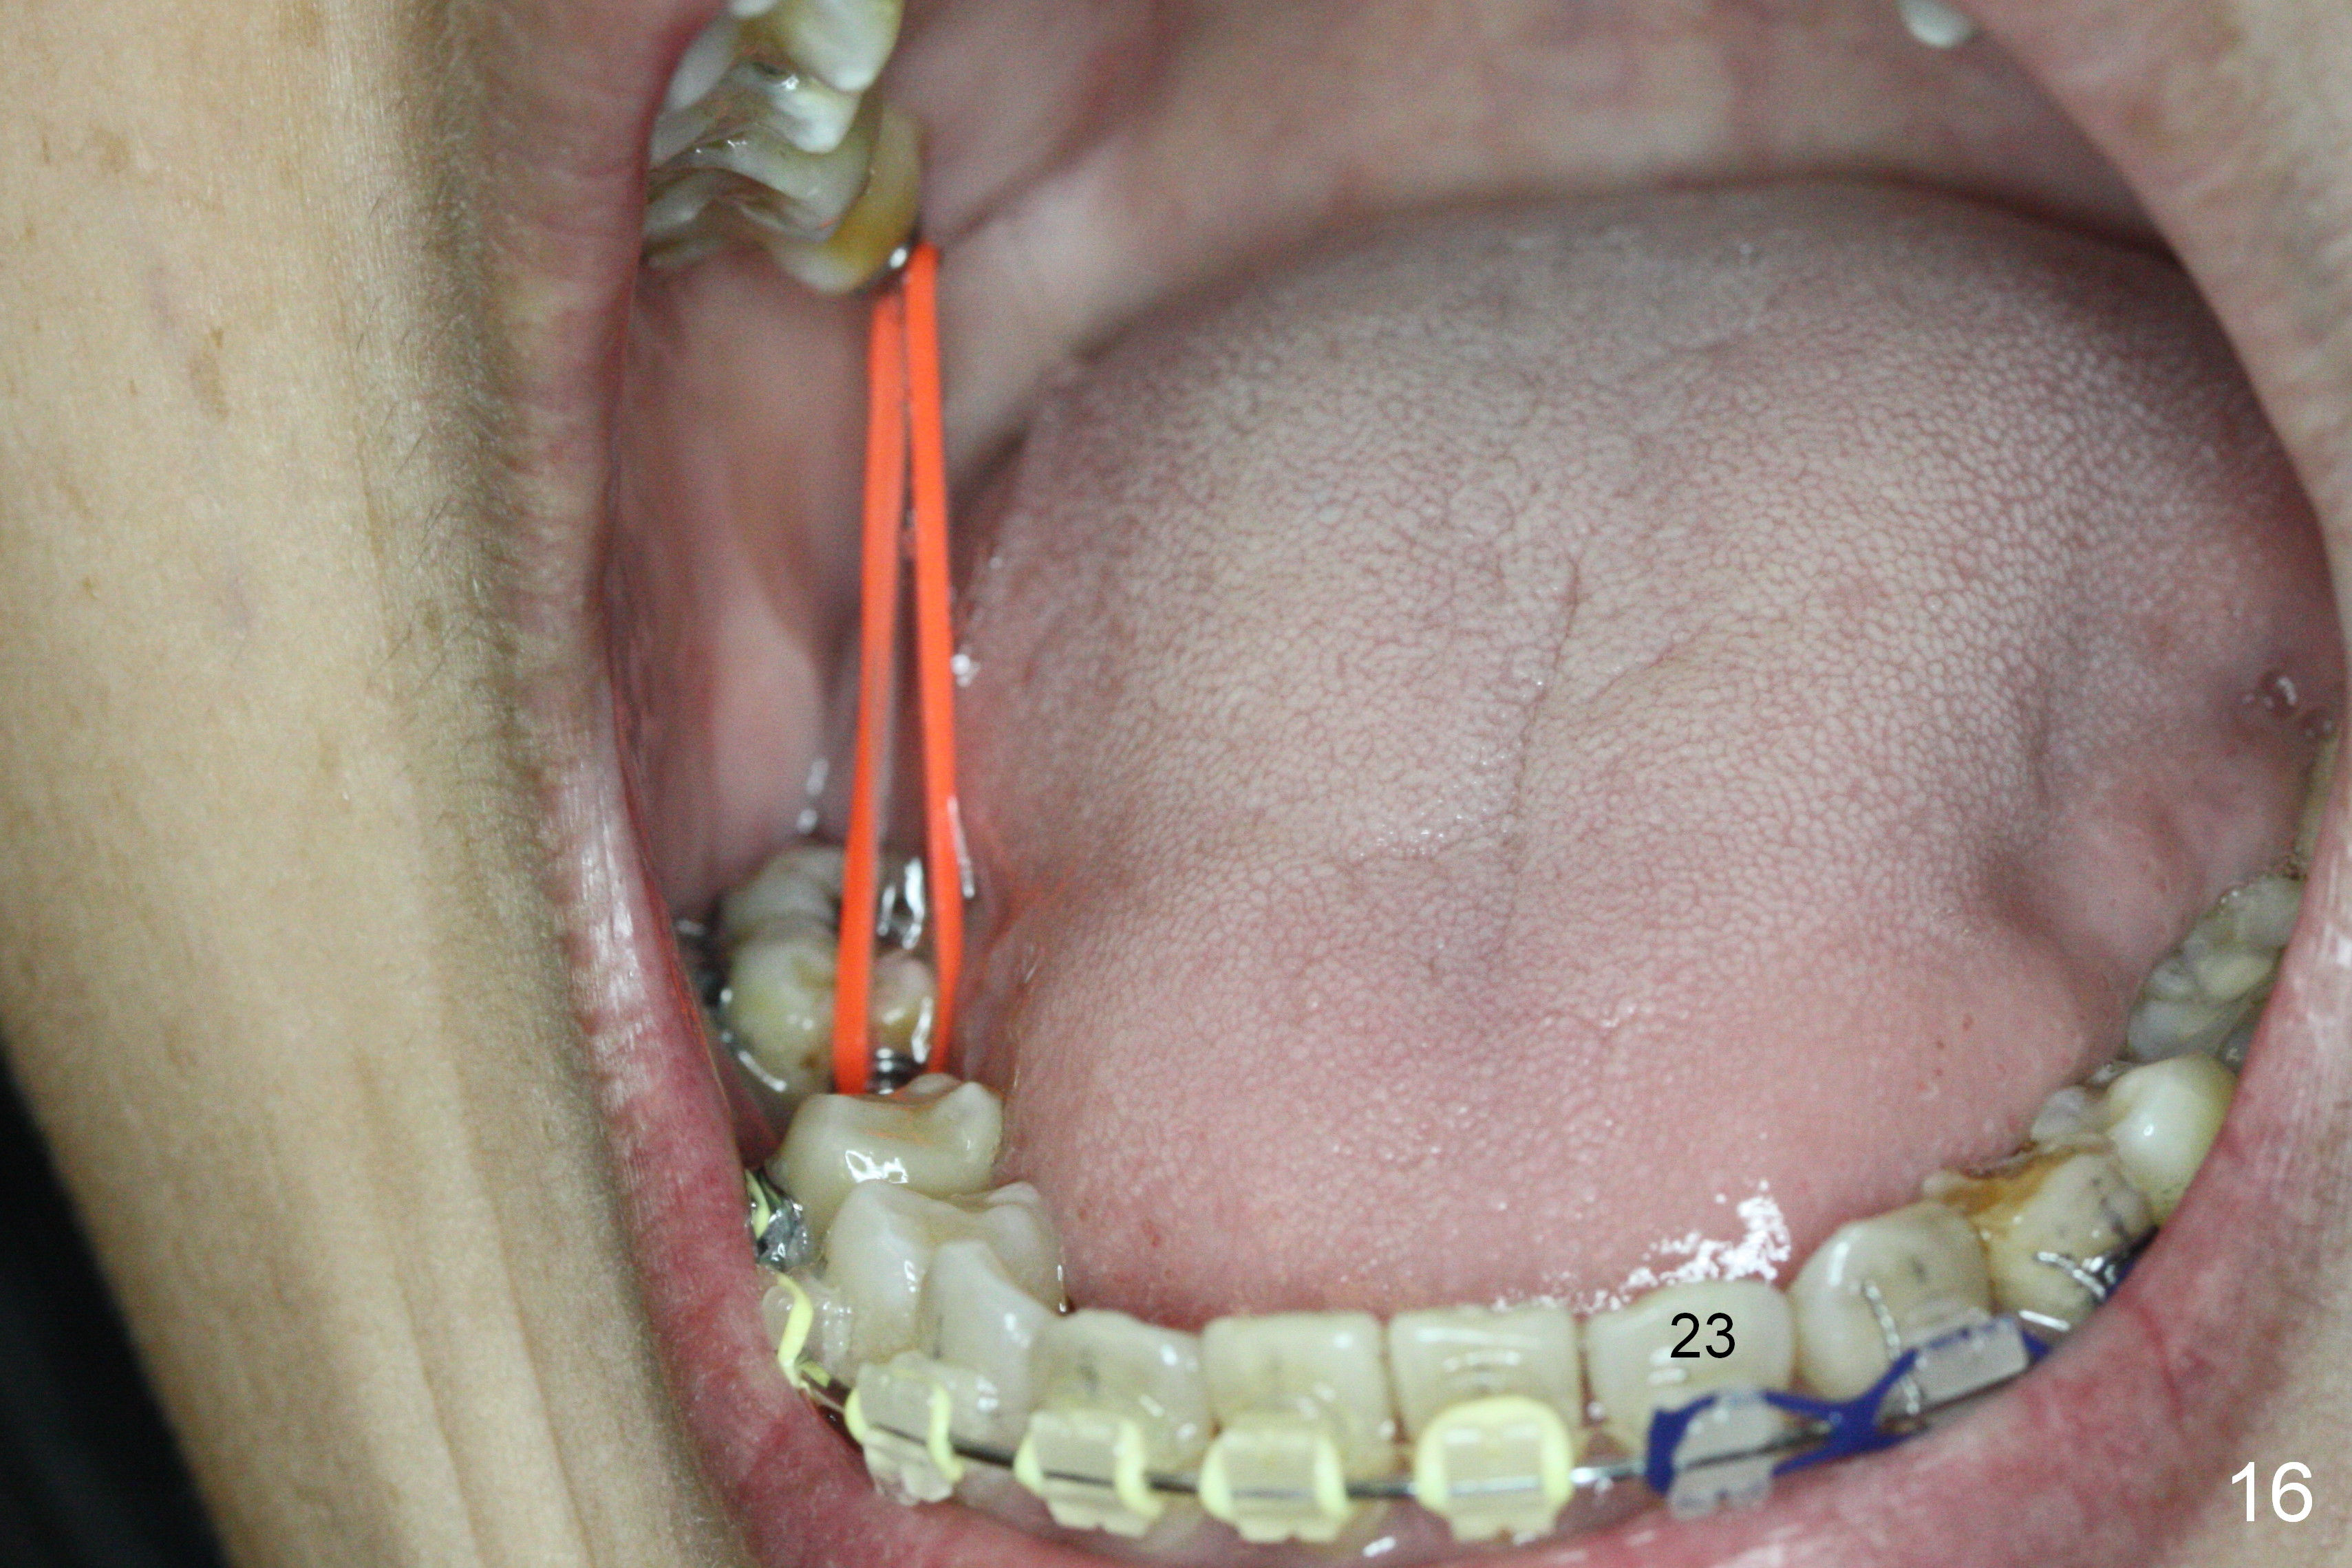

Nearly 6 months post banding, the teeth #20-22 have been distalized (Fig.14). An omega loop has been introduced between #29 and 31 for a month. When the loop is activated, there is pressure upon the tooth #29. It appears that interarch retraction between #2 DL and #31 ML is the most effective (Fig.16).